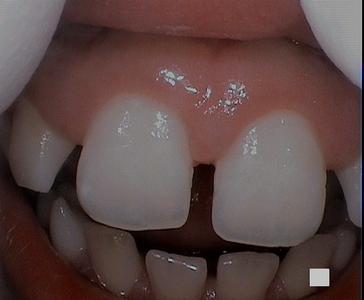

This patient had a benign lesion in between two of their teeth. We were able to remove the lesion via laser dentistry. The patient had fully healed gums after one week!

A piece of gum that has a lesion on it | laser dentistry vienna va patients mouth after a gum lesion has been removed | laser dentist vienna va